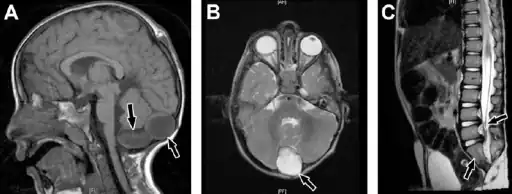

Caudal regression syndrome-a) Brain MRI shows 2 cystic structures at the region of cisterna magna b) cyst is also shown on axial T2-weighted image c) MRI dorsolumbar spine showing abrupt cutoff and bulbar configuration of conus medullaris at the level of L1